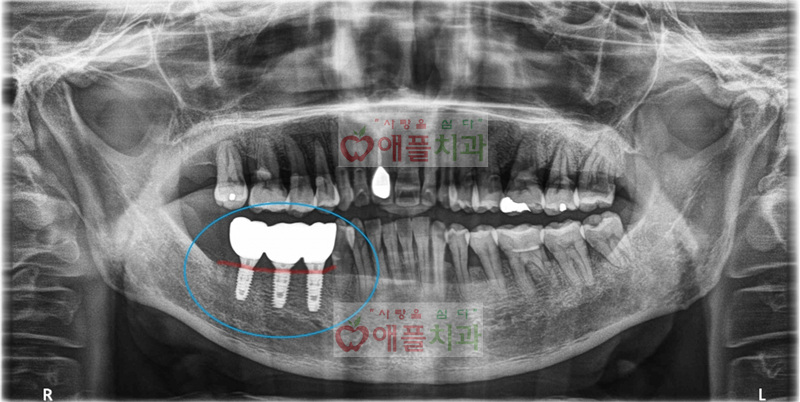

<골이식 + 임플란트 보철 완료후>

우측 아래 어금니가 흔들리고 아파서 내원하셨습니다.

발치후 3개월뒤에 골이식을 동반한 임플란트 동시 식립을 시행하였습니다.

발치된 어금니 뿐만 아니라, 다른 치아 부위에도 잇몸이 많이 안 좋으셔서 잇몸 치료도 진행하신 환자 분입니다.